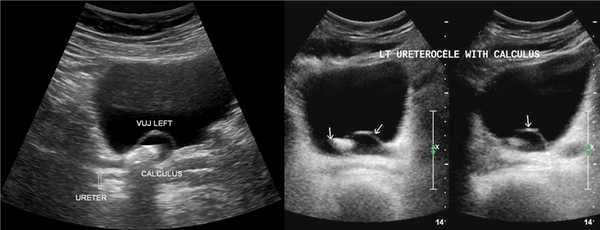

Рисунок. На УЗИ в уретероцеле определяется гиперэхогенная структура с акустической тенью — камень. Уретероцеле может являться одним из факторов, способствующих камнеообразованию.